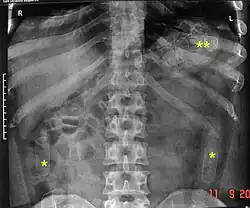

As cavity searches have proven as an ineffective strategy in the total prevention of smuggling objects as it cannot detect objects in the intestines or stomach, as well as taking into consideration the intrusive nature and inherently humiliating or degrading procedure, it has become fairly normal for authorities to instead isolate individuals in a monitored environment until they pass excreta and/or x-ray the individual's pelvic area as it is less invasive and psychologically damaging.